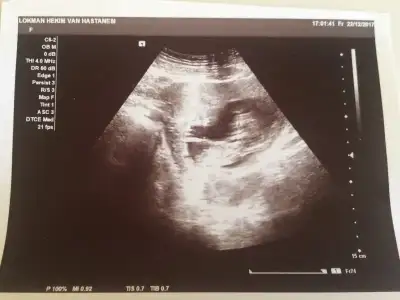

ben baska arkadasa ultrason goruntusunden genital nub tahmini yapmistim tutmus. Ama bir turlu kendiminkini bilemiyorum ya nasil bir kisiligim var anlamadim gitti :KK45: